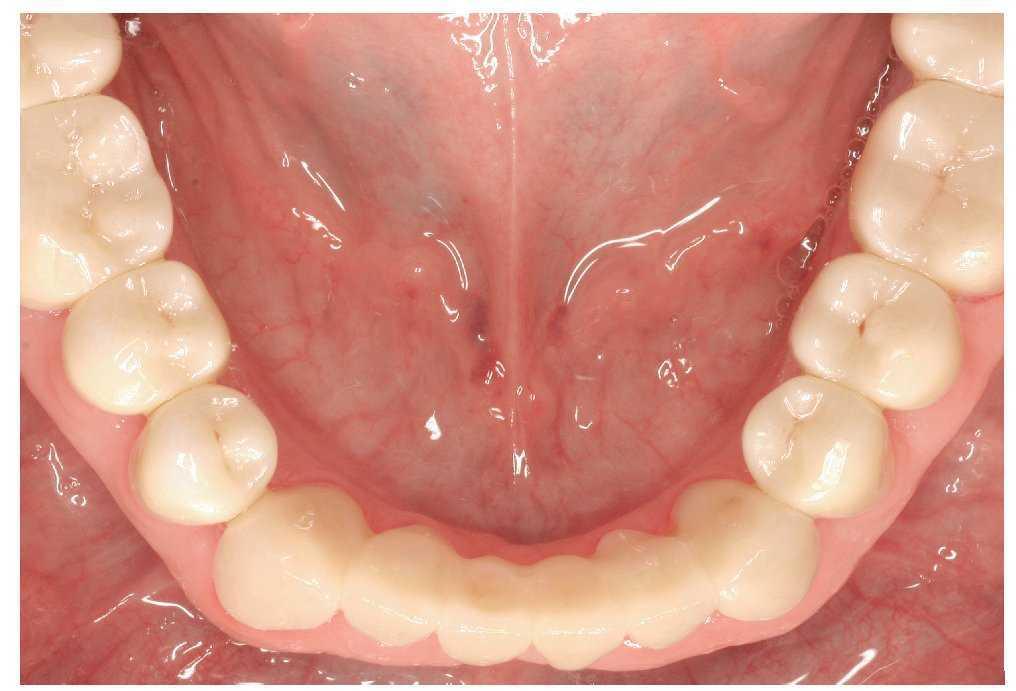

Un paciente de 64 años de edad acudió a la Policlínica Universitaria de Prostodoncia remitido por su odontólogo de cabecera para la rehabilitación protésica de su dentición, que presentaba evidentes muestras de desgaste. La anamnesis general no aportó datos reseñables salvo un diagnóstico de hipertensión. En la anamnesis específica se puso de manifiesto que durante la noche el paciente presentaba rechinamiento y apretamiento dentarios. En la exploración funcional no se observaron molestias musculares ni en las ATM. Sólo se constató un chasquido alternante y ocasional en las articulaciones temporomandibulares. La exploración extraoral reveló una musculatura masticatoria hipertrófica. El paciente presentaba una línea de sonrisa alta, también denominada línea de sonrisa gingival55 (figs. 1 y 2).

Figura 6. Vista oclusal del encerado de la arcada inferior.